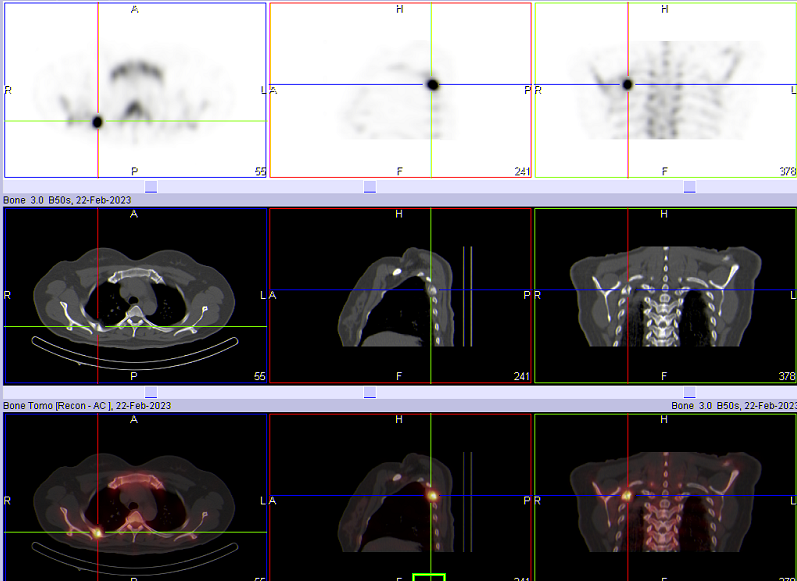

如图所示,一位中年甲状腺癌患者,在术后常规复查全身骨扫描时,发现右侧第4后肋显像剂浓聚灶,单从骨扫描无法明确病灶的准确位置和性质(转移?骨折所致?);进一步加做胸廓断层显像(SPECT/CT)后,影像显示右侧第4后肋局部代谢增高灶,骨质欠连续,局部骨痂形成,诊断为骨折修复期改变。